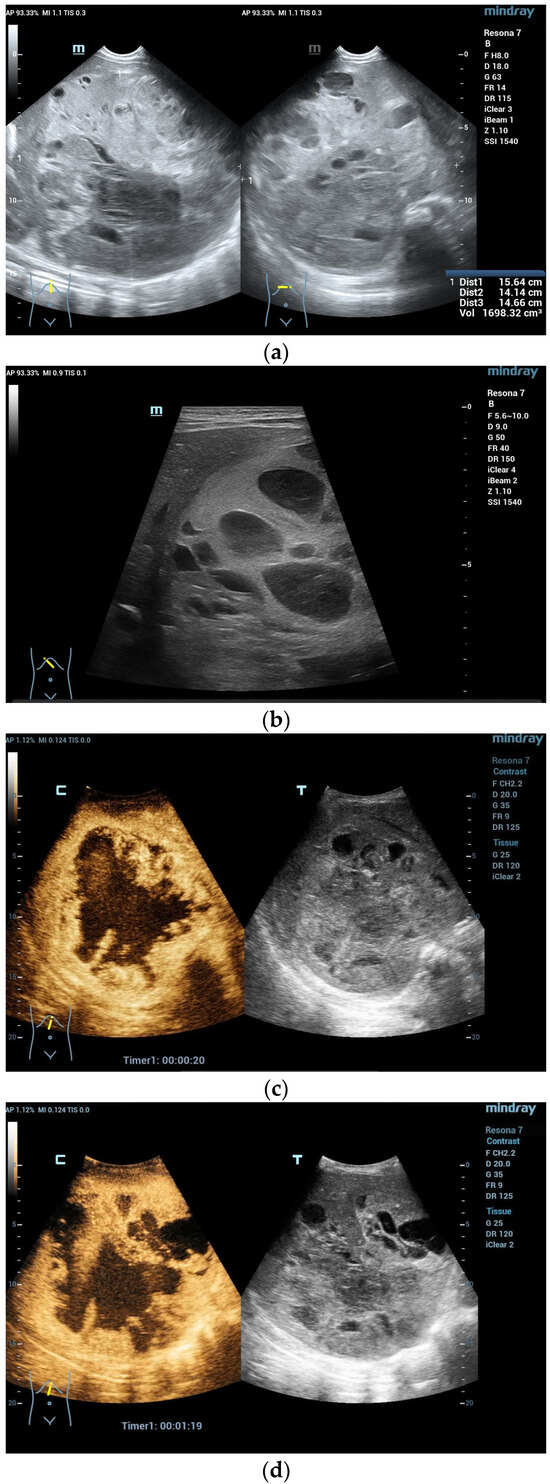

Figure 2.

A 5-year-old boy, presenting with a large mass in the left lobe of the liver. B mode shows a heterogenic mass (a). High resolution B mode with a linear probe clearly reveals multiple cavities representing hemorrhage and necrosis within the mass (b). CEUS in the arterial and early portal venous phases revealed rapid peripheral enhancement with prominent centripetal fill-in and non-enhancing areas (c–e). Late washout after two minutes could be documented (f). Needle biopsy and histological evaluation revealed a highly malignant (G3) liver embryosarcoma.